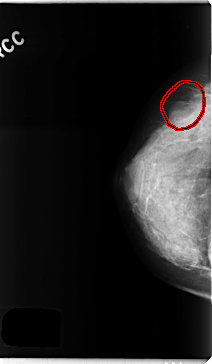

C_0257_1.RIGHT_CC

FILE: C_0257_1.RIGHT_CC.OVERLAY

TOTAL_ABNORMALITIES 1

ABNORMALITY 1

LESION_TYPE MASS SHAPE OVAL MARGINS OBSCURED

ASSESSMENT 4

SUBTLETY 4

PATHOLOGY BENIGN

TOTAL_OUTLINES 1

BOUNDARY

RIGHT_CC LINES 4728 PIXELS_PER_LINE 2752 BITS_PER_PIXEL 12 RESOLUTION 50 OVERLAY